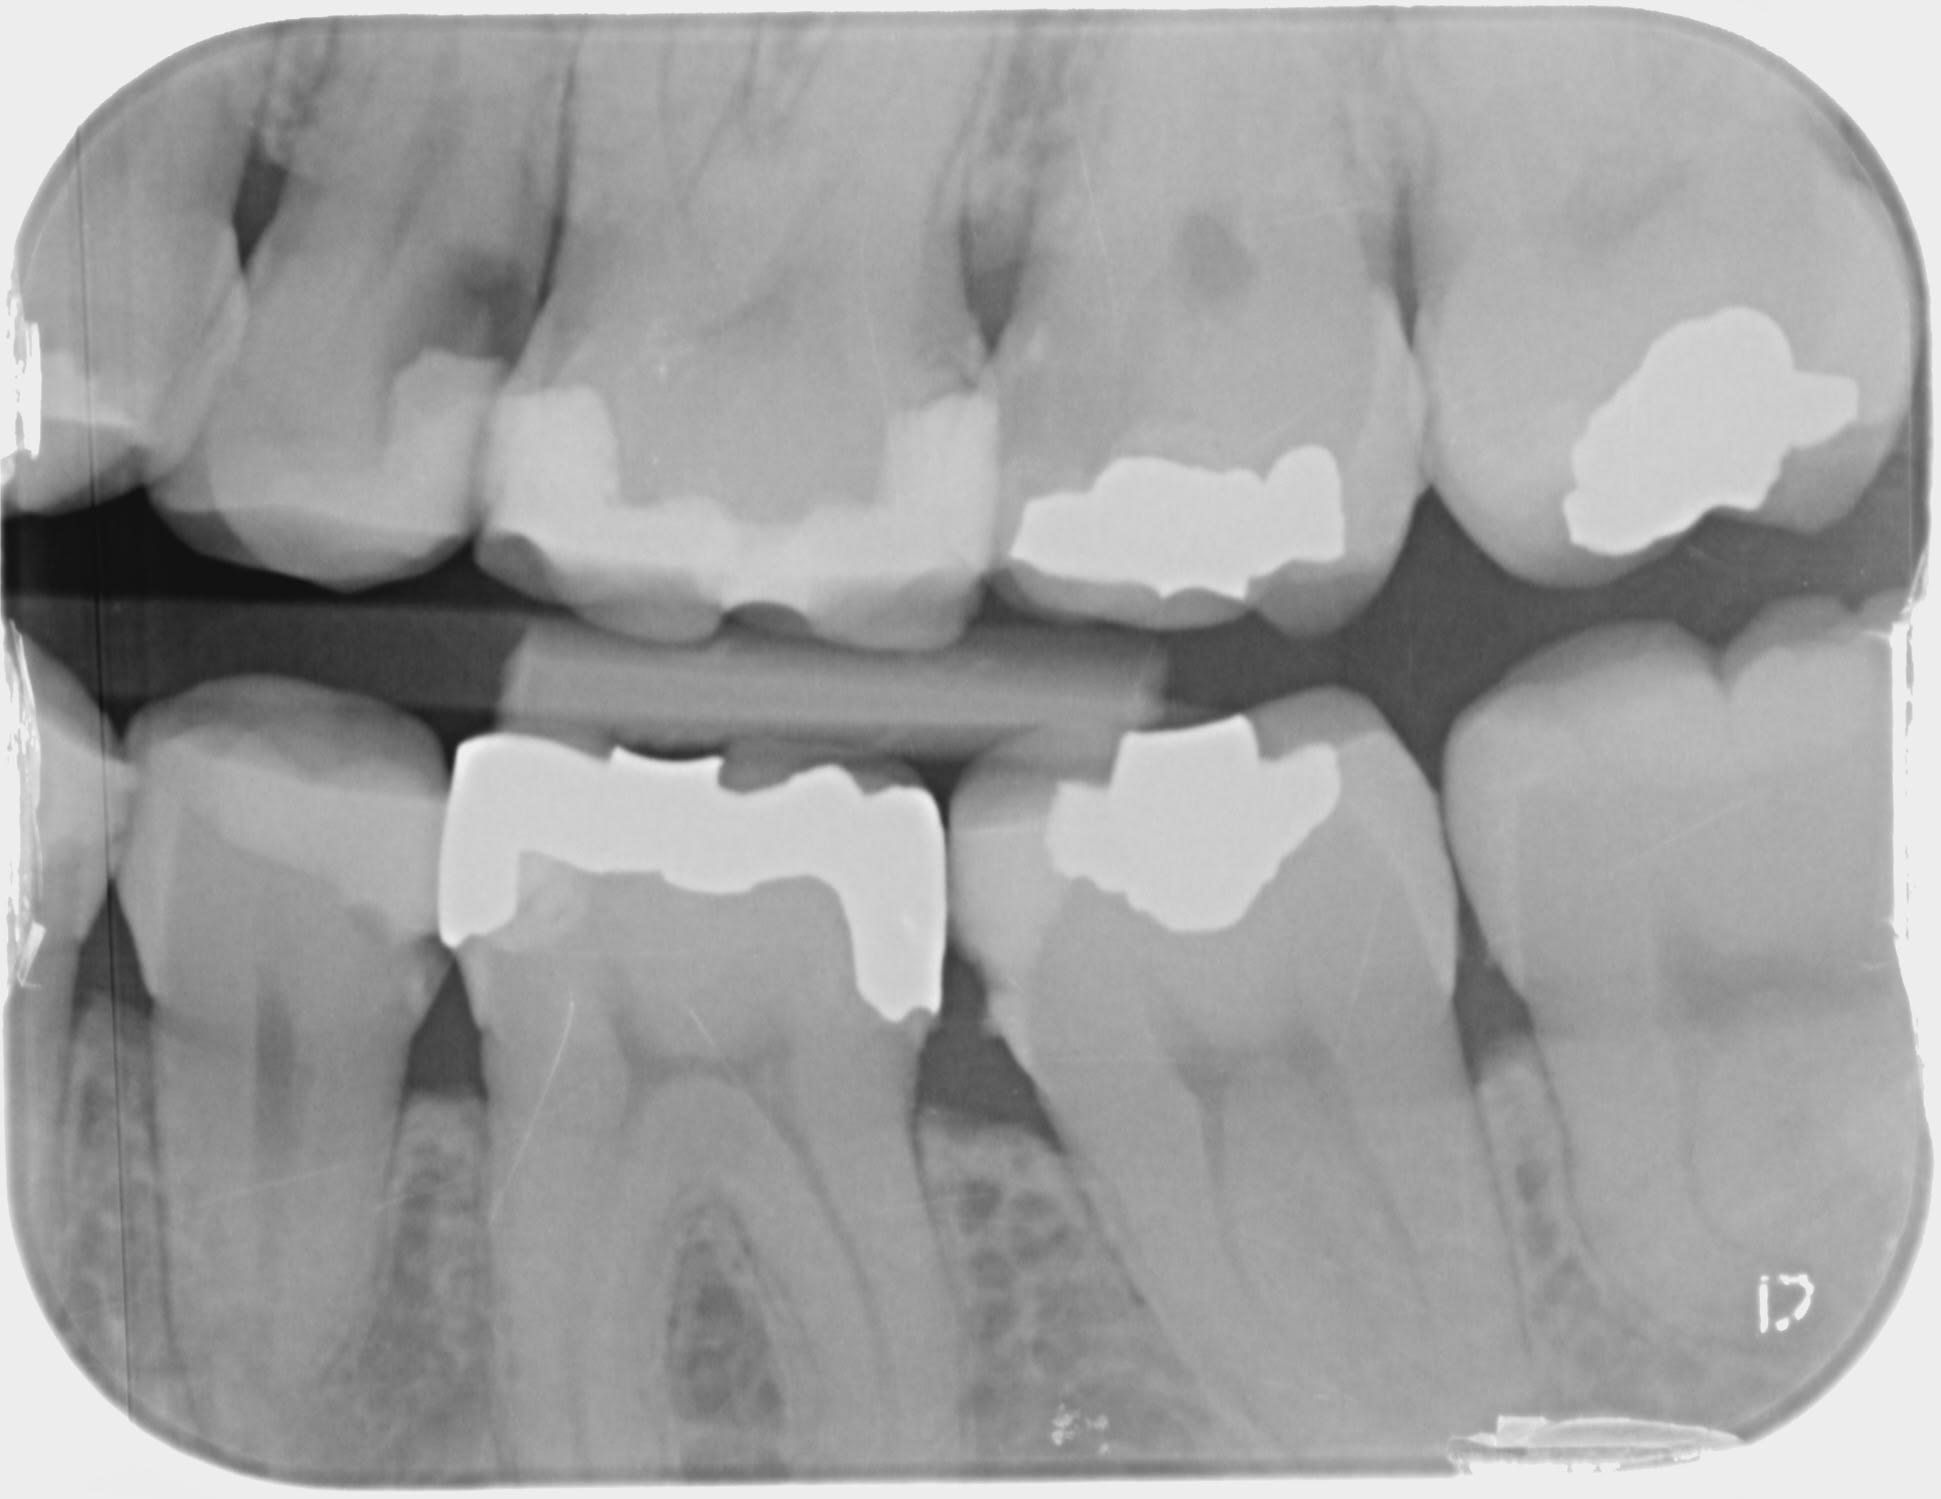

Monsieur X,

Je suis venue à votre cabinet pour 3 consultations en X lors desquelles vous avez traité 2 dents.

Plusieurs mois après ces traitements, les 2 dents soignées continuent de poser des problèmes.

Auriez-vous la gentillesse de me faire parvenir par e-mail les radios (prises avant les soins) qui vous ont amené à poser les diagnostics suivants :

dévitalisation de la dent n° 15;

plombage de la dent n° 17.

Je vous remercie d’avance pour votre aide.

Ce qui m'a amené à poser le diagnostic: tes caries connasse (je l'ai pensé mais pas écris).

Depuis pas de nouvelle.